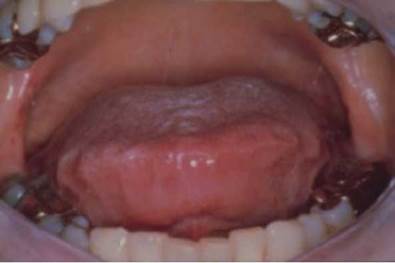

Mediciones cefalométricas revelan que los sujetos con SAHOS tienen cambios significativos en el tamaño y la posición del paladar blando y la úvula; en el volumen y la posición de la lengua; en la posición del hioides, y en la protuberancia maxilomandibular en comparación con los controles. La retrognatia mandibular y micrognatia (Figura 2 y 3) hacen que que la lengua descanse en una posición más superior y posterior, con incidencia sobre la VAS. Una lengua festoneada (Figura 9) puede acompañar la micrognatia. Los hombres con retrognatia o micrognatia se pueden dejar crecer la barba para compensar esta variante anatómica. Dientes apiñados de forma horizontal con dientes inferiores excesivamente posteriores a los superiores (overjet) a menudo acompañan la retrognatia o micrognatia.

Lengua festoneada en un paciente con síndrome de apnea-hipopnea obstructiva del sueño y amiloidosis.

Figura 9: Lengua festoneada en un paciente con síndrome de apnea-hipopnea obstructiva del sueño y amiloidosis.

Fuente: Archivo personal de la autora KJPG.